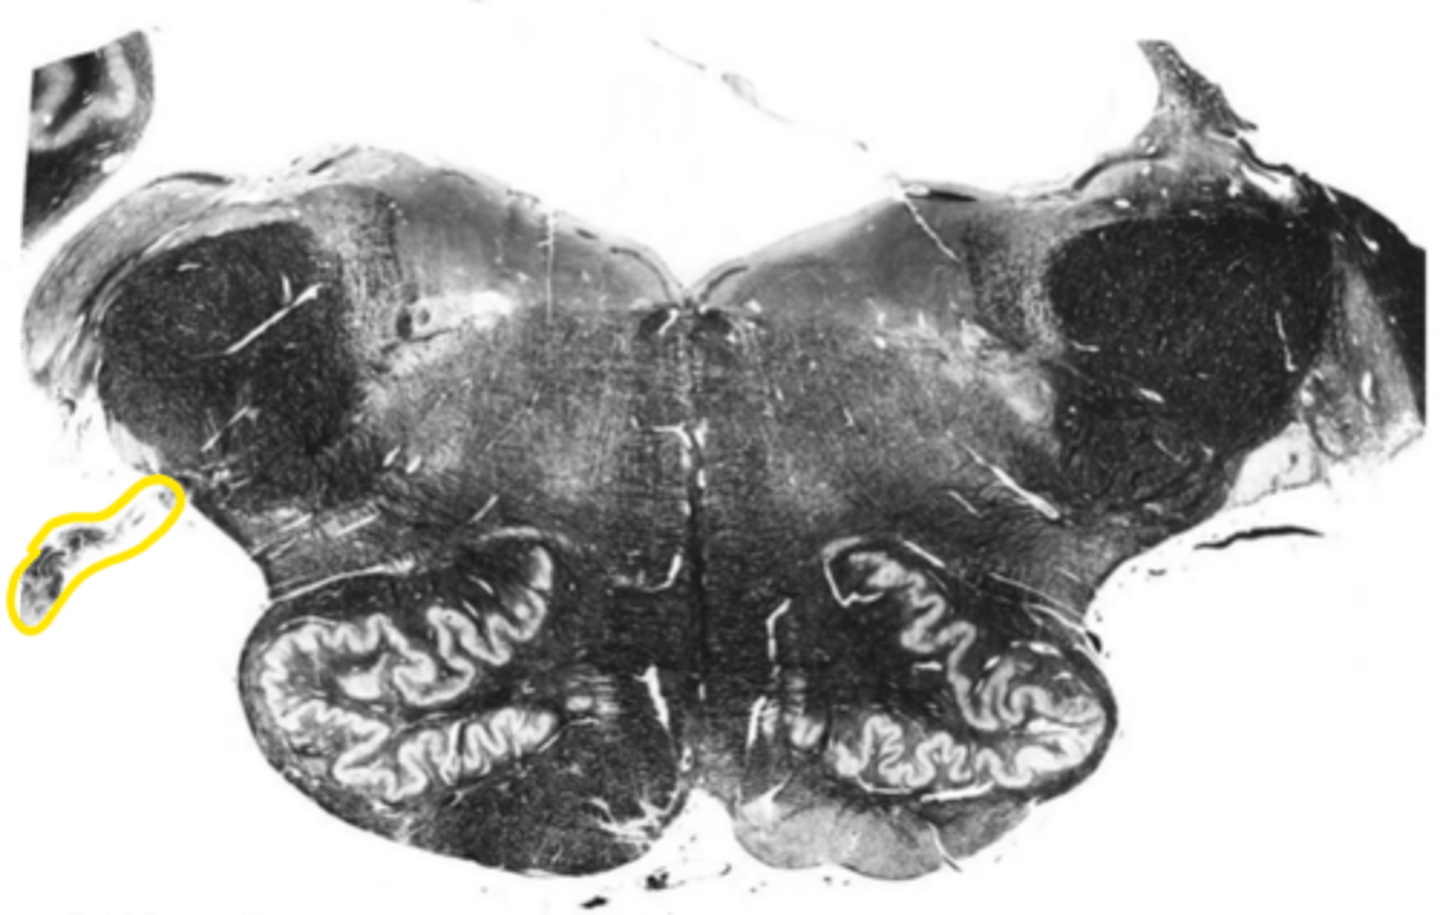

closed medulla

ID the brainstem level